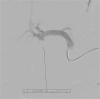

The pseudoaneurysms of the cystic artery (CAP) are very uncommon. They usually develop as a result of an acute cholecystitis or after a cholecystectomy. Among the complications, we can find hemorrhaging, biliary blockage, and haemobilia. Limited understanding of the illness makes managing specific cases difficult. We describe a case of a cystic artery pseudoaneurysm complicating an acute cholecystitis that was successfully treated by transcatheter arterial embolization.